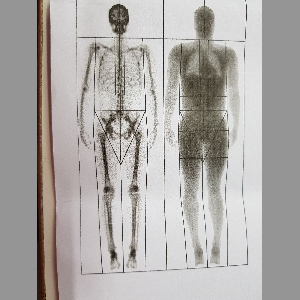

What is DEXA scan?

Updates the reader on DEXA scan and its utilities.

What is DEXA scan?

Updates the reader on DEXA scan and its utilities.